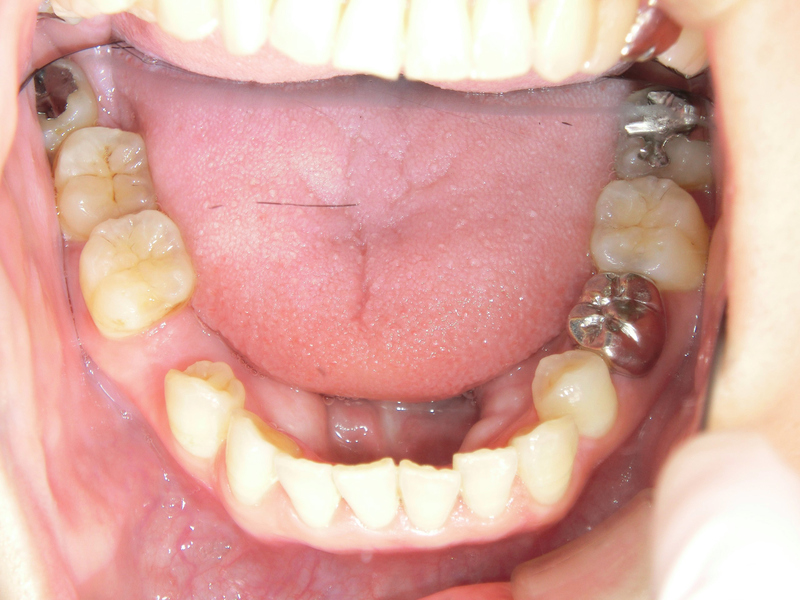

ではどのような治療法か、画像を用いて解説していきます。

まずはインプラントを入れる部位を肉眼的に確認します。そしてインプラントを埋め込む顎の骨と周囲の歯については、レントゲン写真やCTを用いてそのいい関係や性状を確認していきます。